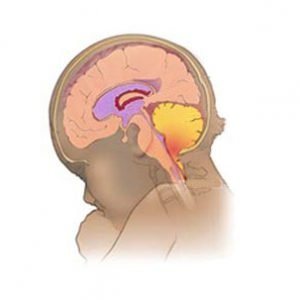

Аномалия Арнольда-Киари: MRI снимки